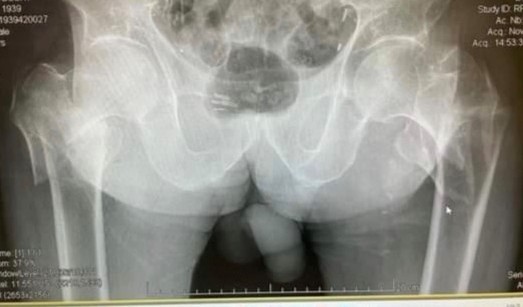

An 85-year-old male patient who was hit by a car as a pedestrian presented at our emergency department. The patient has a medical history of chronic obstructive pulmonary disease and compensated chronic cardiomyopathy. He lives with his son and could independently perform daily activities. On examination, external rotation and shortened lower limbs on both sides were evident, as well as pain in palpation and/or mobilization of the lower extremities bilaterally. Following the radiological study, a transtrochanteric fracture of the right femur and a subtrochanteric fracture of the left femur were revealed (Fig. 1).

Figure 1: Anteroposterior view of the pelvis. Right intertrochanteric fracture. Left subtrochanteric fracture.